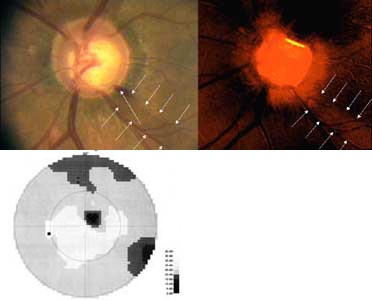

Výpadek nervových vláken začíná temporálně dole, kde je na terči patrný zálom vény. Na barevné fotografii není viditelný, protože se jedná o výpadek v hlubší vrstvě nervových vláken, která je překryta vlákny neporušenými. Tato hluboká vlákna směřují do temporální dolní části makuly a v zorném poli jim odpovídá horní nasální skok.